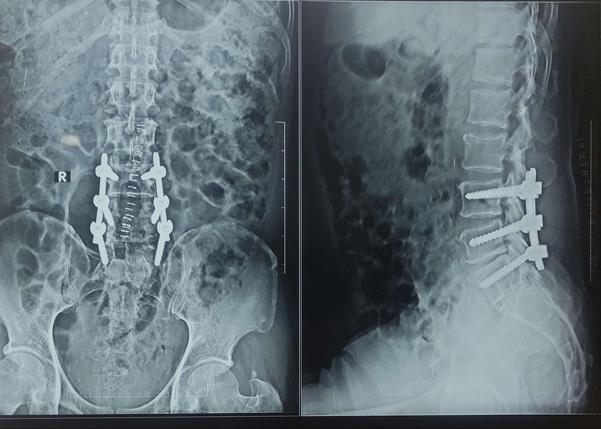

L3-L4, L4-L5 DISC PROLAPSE, SEVERE SPINAL CANAL STENOSIS –SPINAL FIXATION & DECOMPRESSION DISCECTOMY

View Details